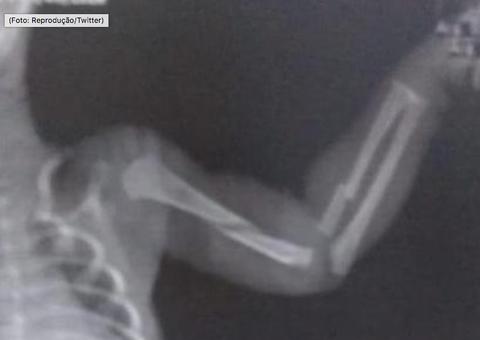

Ele foi baleado e segundo o site R7 não resistiu aos ferimentos e morreu no hospital.